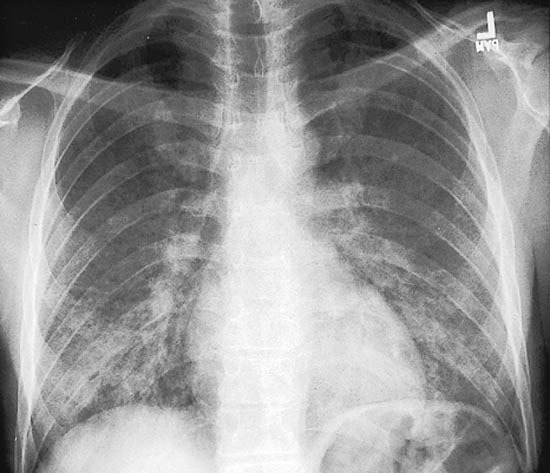

Paciente, HIV positivo, CD4 < 200, com quadro de febre, tosse seca, dispneia progressiva, ausculta normal e rx de tórax mostrando infiltrado bilateral, peri-hilar, poupanco ápices…

Diagnóstico, achados sugestivos, tratamento e profilaxia?

PNEUMOCISTOSE (PCP)

Agente: pneumocystis jirovecii

CD4 < 200

Pneumonia arrastada, candidiase, hipoxemia, aumento LDH

Rx de tórax: infiltrado bilateral, peri-hilar, poupanco ápices

Tratamento: SMX-TMP IV/VO 21 dias (mesmo antes do isolamento do agente por escarro ou lavado bronquico)

Se paO2 < 70 em AA: + corticoide

Profilaxia 1a com SMX-TMP 3x/sem: CD4 < 200, candidiase oral, febre > 2 sem